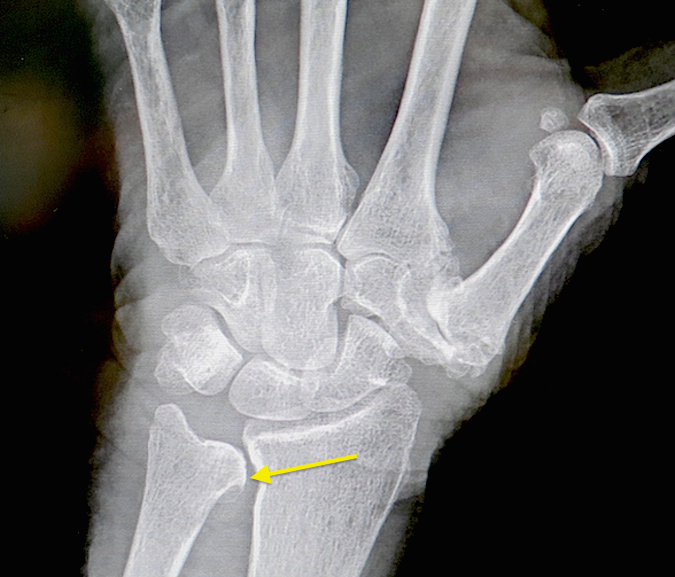

Last week I went for an MRI. X-Rays, ultrasound and MRI results indicate I have Vaughan-Jackson Syndrome (extensor tenosynovitis) which is characterized by the disruption of the digital extensor tendons, beginning on the ulnar side with the extensor digiti minimi (pinky finger) and extensor digitorum communis tendon of the pinky finger; the tendon is primarily responsible for straightening the index, middle, ring and pinky fingers. In some cases, the tendon may rupture, requiring surgery; so far my tendon is in tact. Vaughan-Jackson is most commonly associated with rheumatoid arthritis. I was never told I have rheumatoid arthritis and since 2003, I have been treated for osteoarthritis.